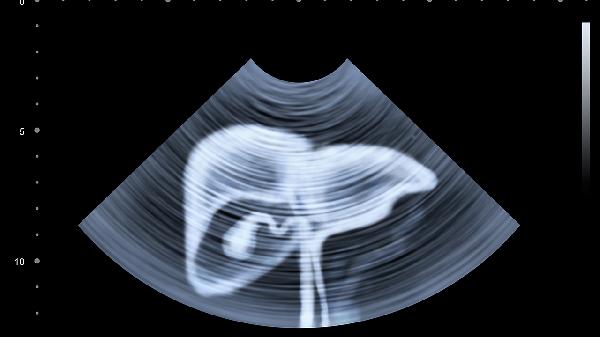

保護(hù)肝臟主要有調(diào)整飲食、控制飲酒、規(guī)律作息、合理用藥四種方法。肝臟是人體重要的代謝器官,通過科學(xué)的生活方式干預(yù)可降低肝臟損傷風(fēng)險(xiǎn)。